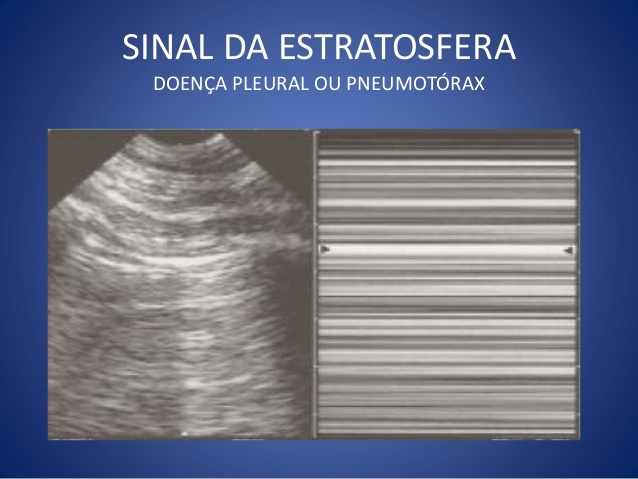

Como o E-FAST pode auxiliar no diagnóstico de pneumotórax (o que ele mostra)?

Ausência de movimentação entre os folheto pleurais por interposição gasosa

Normal: sinal da praia (deslizamento livre entre as pleuras pulmonares)